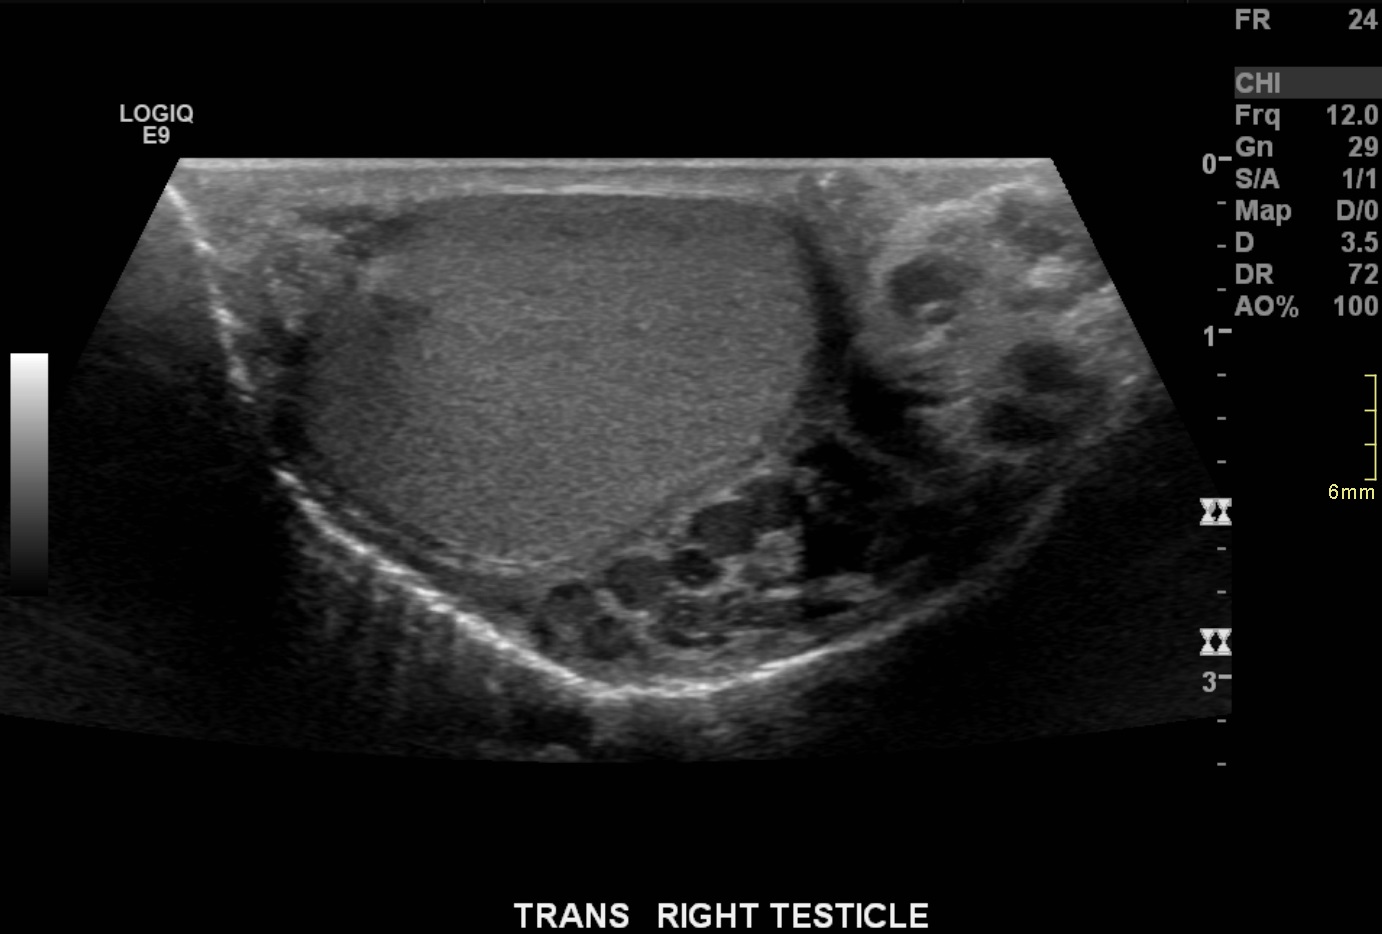

Ultrasound demonstrates enlarged veins (>3 mm) adjacent to the testicle. Angiogram demonstrates reflux of contrast into the left gonadal vein to the level of the scrotum, indicating venous valvular incompetence. Coil embolization and sotradecol sclerotherapy of the left gonadal vein were performed, with an Amplatzer plug at the top of the vein. Repeat angiogram demonstrates no contrast opacification of the vein. Red arrows indicate the left gonadal vein and the blue arrows indicate the left renal vein.